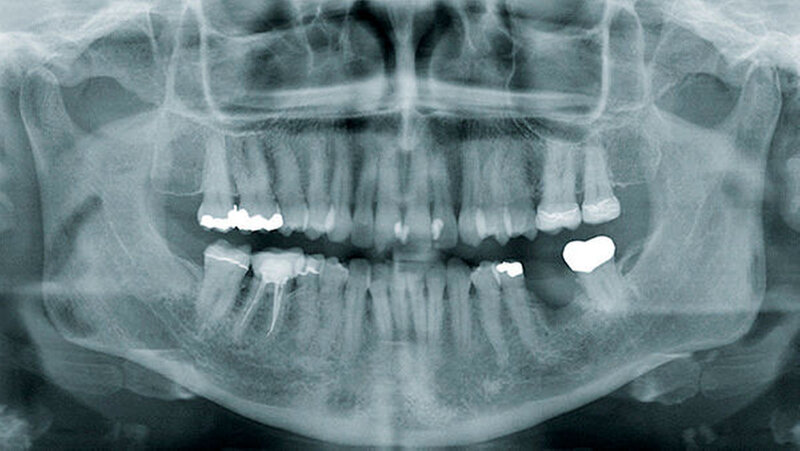

Die konventionelle Panoramaschichtaufnahme (PSA) hat als Ausgangsuntersuchung weiterhin einen großen klinischen Stellenwert (Abbildungen 1 und 3). Sie gibt einen ersten Überblick über Knochenstruktur und Zahnstatus. Ihre Aussagekraft ist jedoch aufgrund von Überlagerungseffekten limitiert [Strobel et al., 2012]. Darüber hinaus ist sie nicht sehr sensitiv, da erst ab einem Knochensubstanzverlust von etwa 30 bis 50 Prozent eine Osteolyse im Röntgenbild erkennbar ist.

Neben den bekannten Bisphosphonaten werden zunehmend Fälle von Kiefernekrosen auch durch Denosumab, einen RANKL-Antagonisten, beobachtet. Deswegen sollte speziell auch nach den Medikamenten Prolia©und XGeva©vor oralchirurgischen Eingriffen gefragt werden. Während Prolia©in der Osteoporosetherapie Anwendung findet, wird XGeva©bei Prostata- und Mammakarzinompatienten subkutan verabreicht und hat speziell auch bei Nierenfunktionsstörungen seine Indikationen. Die Halbwertszeit von Bisphosphonaten beträgt bis zu zehn Jahren, die von Denosumab in der Regel zwischen 80 und 120 Tagen [Ruggiero, 2013]. In direkten Vergleichsstudien bei onkologischen Patienten werden etwas mehr gehäuft Nekrosen durch Denosumab als durch Zoledronat (Aminobisphosphonat) festgestellt. Die Erfolge einer definitiven Heilung waren jedoch bei den Denosumabnekrosen scheinbar besser [Saad et al., 2012; Van Wyngaert et al., 2011]. Als Hauptursachen einer Kiefernekrose sind bei beiden Präparaten nach wie vor Zahnextraktionen zu nennen. Das zweitgrößte Risiko durch Prothesendruckstellen wird jedoch häufig unterschätzt (Abbildungen 5 und 6) [Hoefert, 2012].